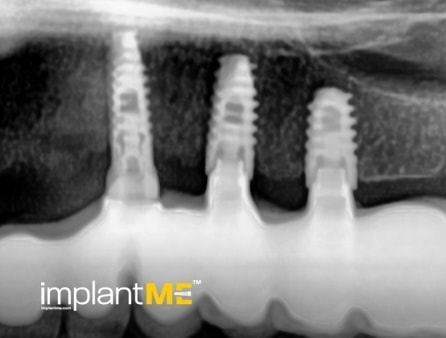

Атрактивните и особено здравите заби не се само одлучувачки дел од нашиот изглед, туку и на нашата личност. Во минатото, губењето на еден или повеќе заби имаше одлучувачка улога врз изгледот на луѓето. Поради модерната орална имплантологија, ова повеќе не е случај. Со релативно мали процедури за орална хирургија, индивидуалните или сите непостоечки заби можат да бидат заменети со импланти, естетски и функционално еднакви на природните заби. Преку вметнување импланти во форма на корен, можно е да се избегнат промени на соседните заби и да се зацврстат коронки што тешко може да се разликуваат од вистински заби во празнините на забите. Коронките или мостовите поддржани од импланти се прицврстени на колец зацврстен во коска, што им дава на пациентите џвакање со чувство скоро нималку различно од нивните заби. Во случај на потполна беззабост, имплантите може да претставуваат сигурна потпора за мобилна протеза, како и за големи фиксни мостови.

Забната протетика поддржана од имплант тесно се доближува до природните заби. Коронките водат со нивниот природен изглед, имплантите со нивната стабилност, а двете заедно со нивното позитивно влијание врз функционалното зачувување на целиот мастикаторен апарат.